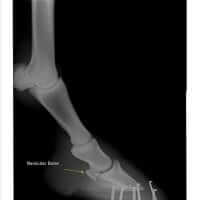

Navicular Disease In the Horse

Equine Navicular Disease has many names, including Navicular Syndrome, caudle heel pain as well as podotrochleosis.  The condition is all too common to many horse owners, unfortunately, and can significantly impact performance, general movement and overall quality of life due to pain generally located in the heel region of the front feet.  Navicular Syndrome can be difficult to manage, especially in the advanced stage, but through a combination of approaches, including nutrion and herbs, the outcome for the patient can be improved.